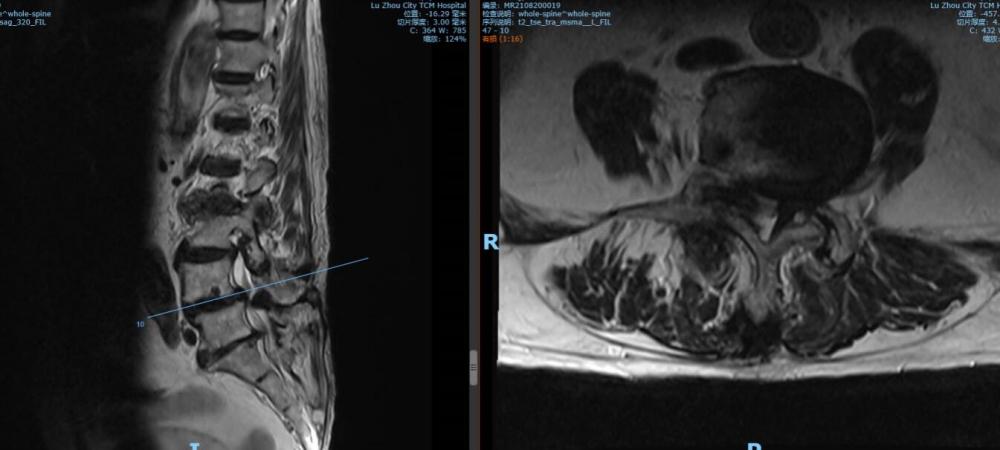

腰4 5椎間盤MRI

腰5 骶1椎間盤MRI